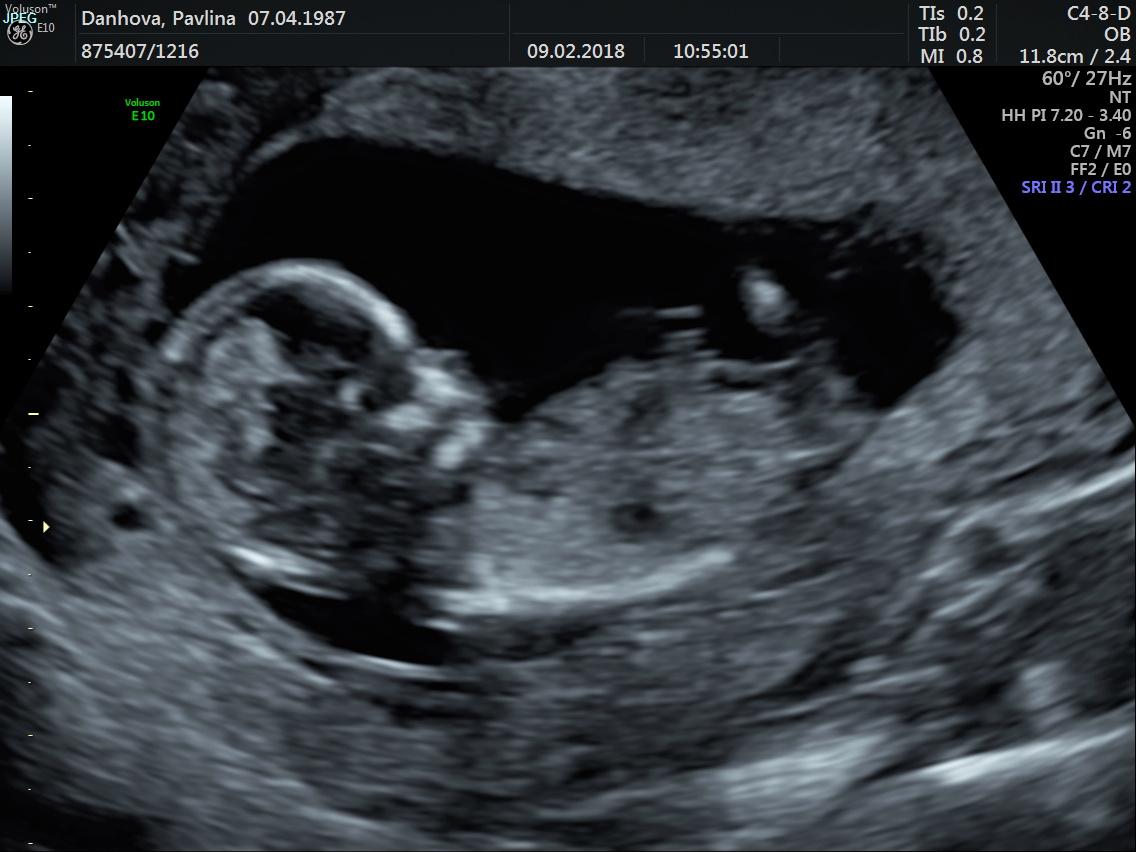

@2hanah Je tam vidět jen pohlavní hrbolek 🙂. Pohlavi se určuje podle jeho sklonu. Když směřuje nahoru, tak kluk, když rovnoběžně se zakřivením páteře, tak holka. Na velký ultrazvuk jdu az za 2 týdny 🙂. Ovšem zatím většina tipovala holcicku... Sama jsem zvědavá, co to je... Na druhou stranu přemýšlím, jestli si nenechat překvapeni do porodu 🙂

Ja z toho našeho ke konci 13tt nepoznam nic ☹